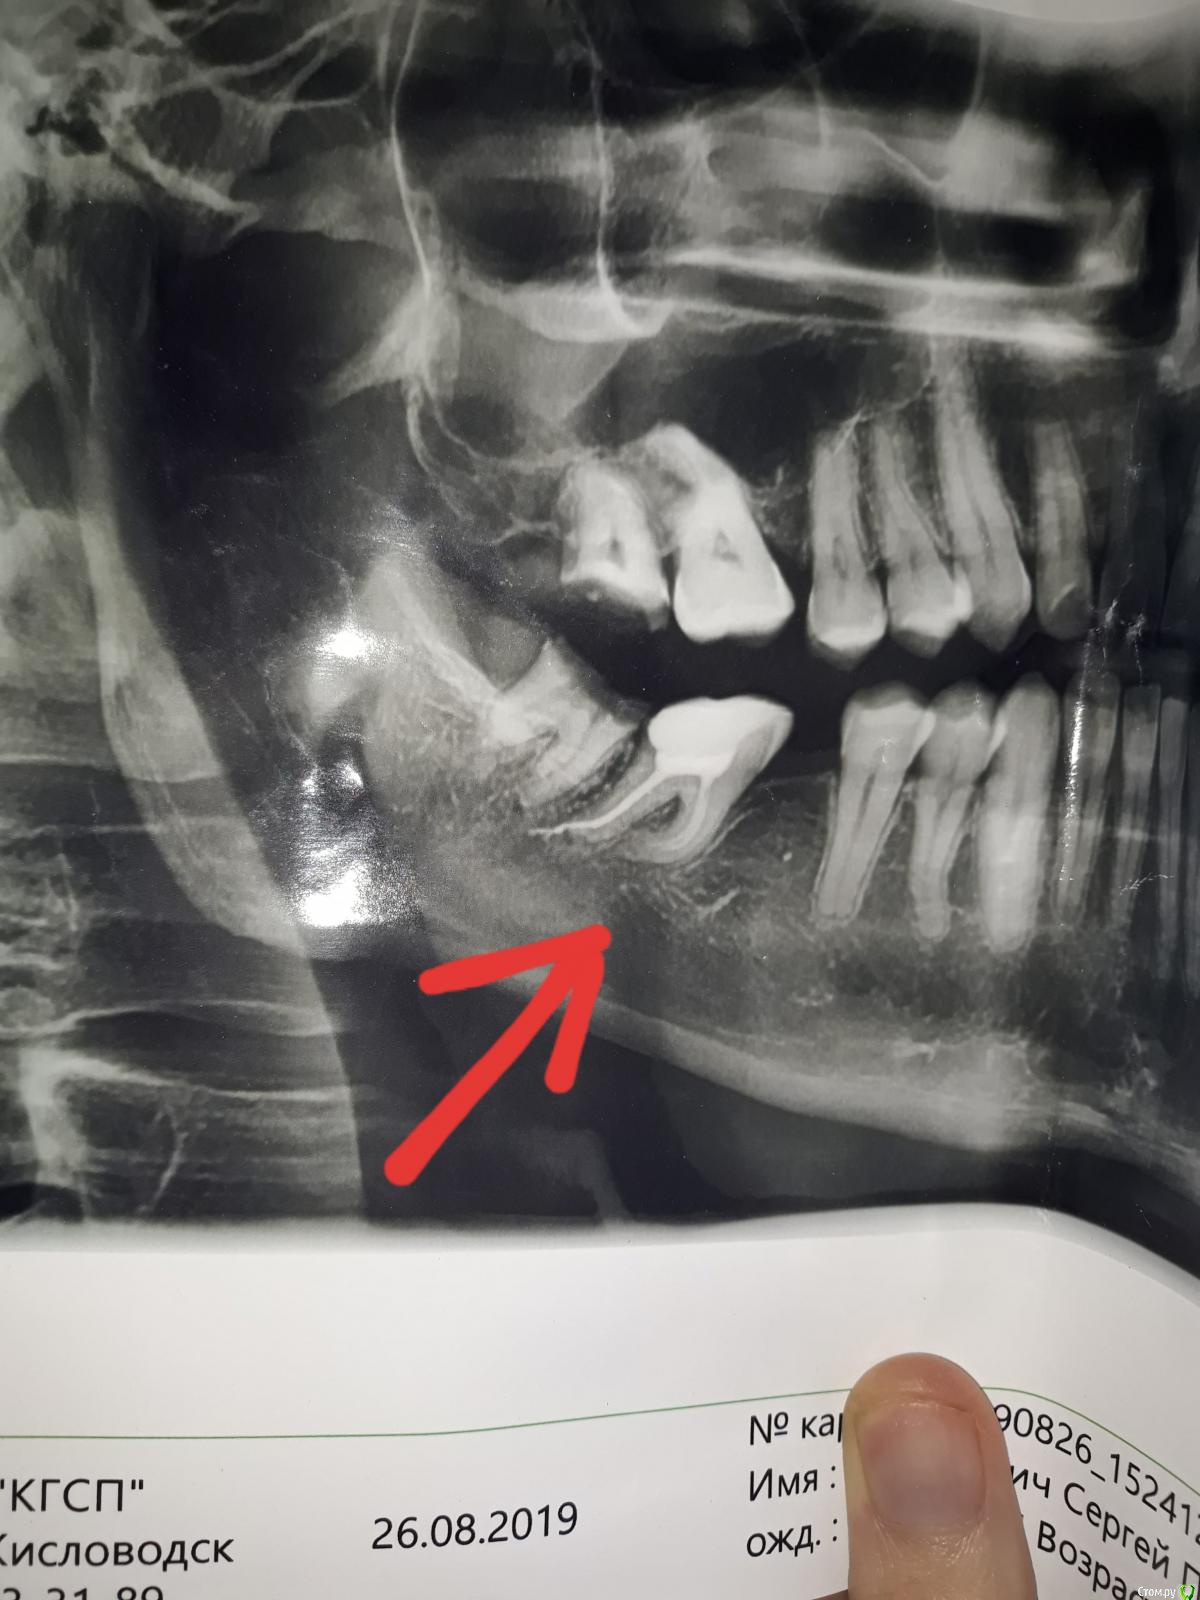

Здравствуйте, уважаемые специалисты, подскажите пожалуйста коронку (металлокерамика) на 47зуб в моем случае лучше ставить на вкладке или на штифте? Один доктор говорит можно и на штифт, а другой что штифтовые конструкции разваливаются за 3-4 года. 48 уже удален. Заранее спасибо за ответ.